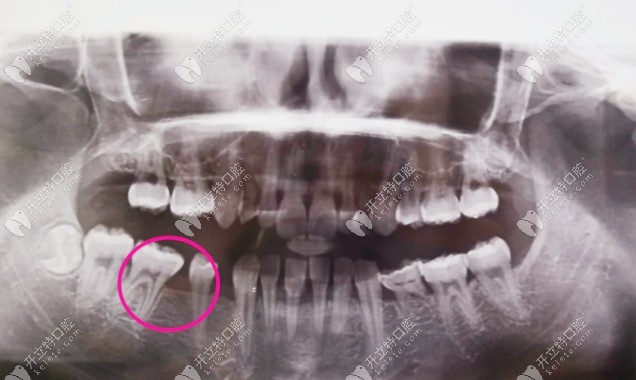

這是我到牙科拍的片子,大家應(yīng)該能看出來(lái)掉了兩顆吧,牙齒很不好,還有牙結(jié)石▼

牙齒拍片子的照片